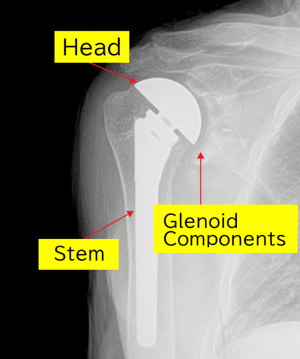

Artificial joint replacement surgery involves inserting the following instruments into the scapula and humerus of the shoulder, as shown in the illustration. Please refer to the illustration. For the deformed humerus, a metal ball (head) and rod (stem) are inserted into the humerus. A plastic socket (illustration right, glenoid component) is placed into the glenoid cavity of the scapula. The plastic socket is typically fixed in place with an adhesive called bone cement.

The diagram below shows the artificial joint inserted into the humerus and scapula. The stem and head are connected.

The diagram below shows the plastic socket (plastic component, referred to by doctors as the glenoid component) inserted into the glenoid cavity of the scapula.

X-ray after surgery